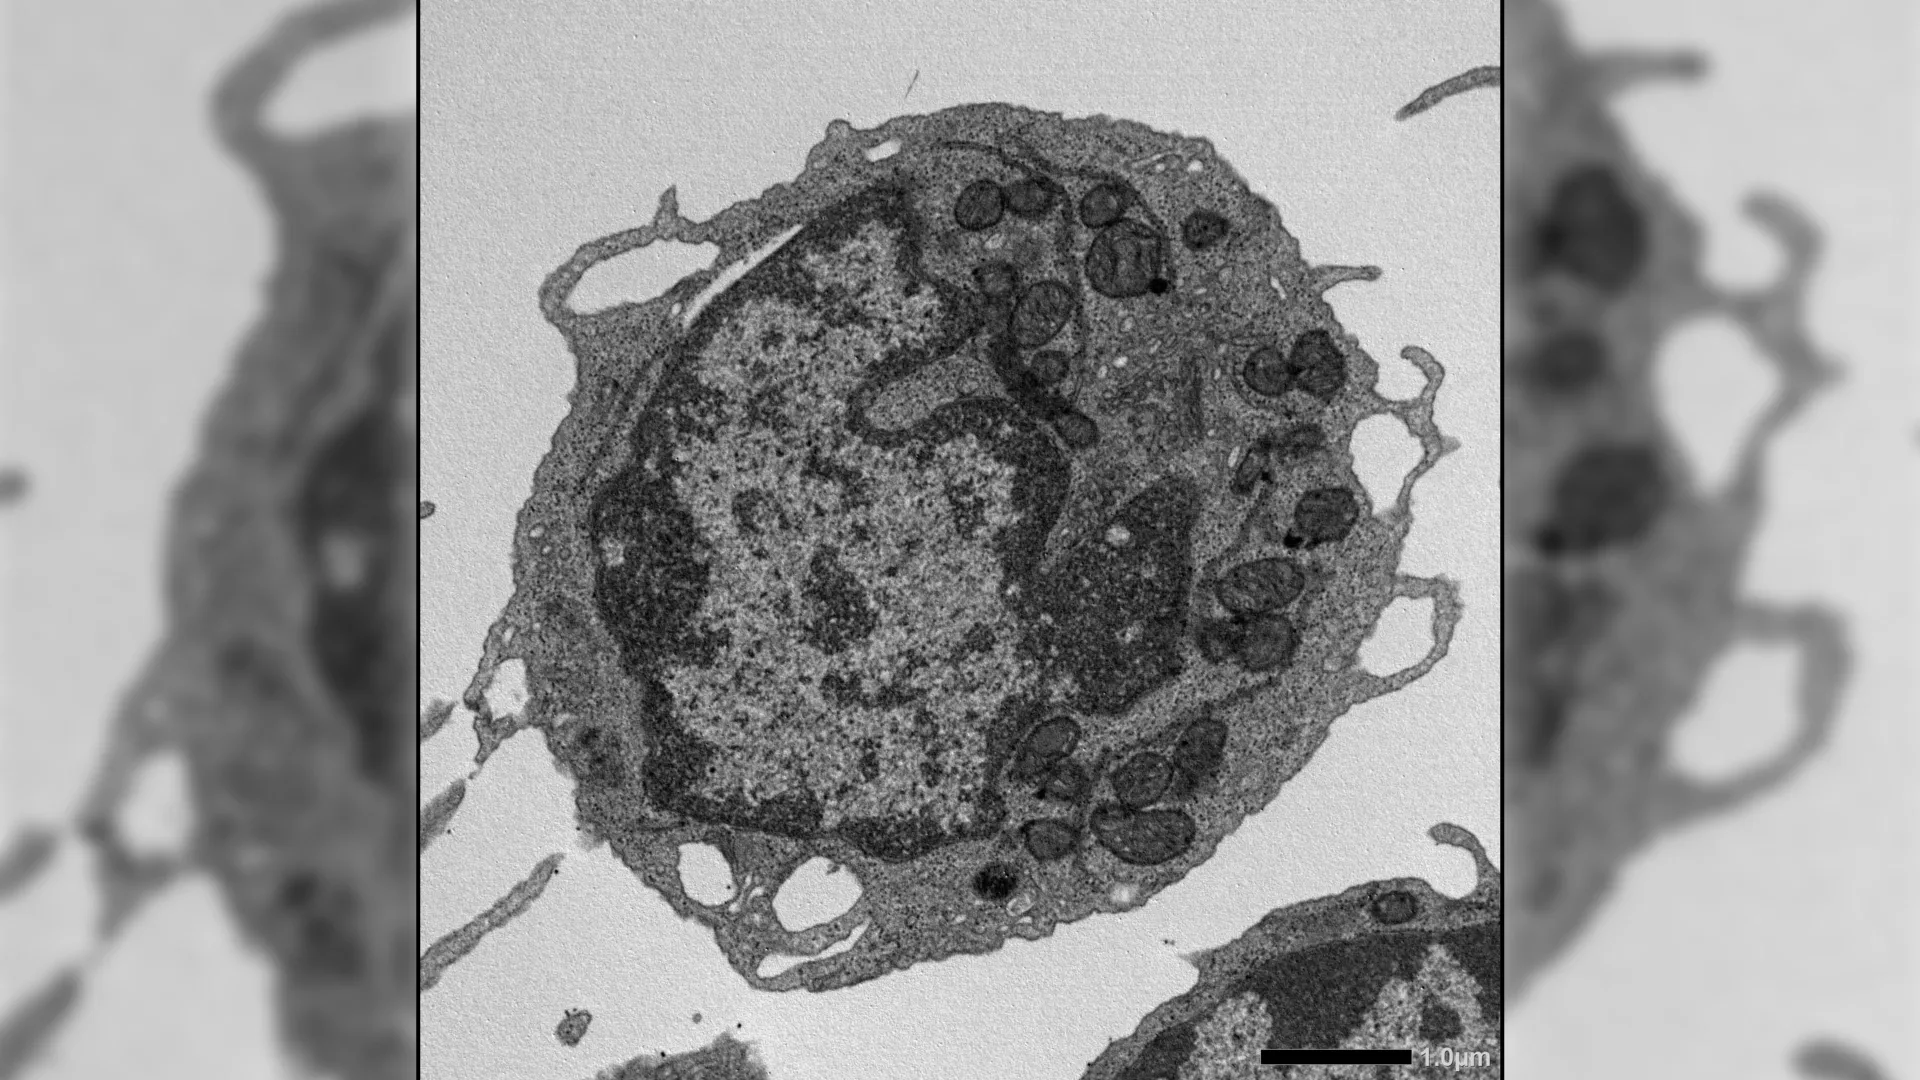

Researchers in Brazil are advancing a promising form of cancer immunotherapy by making natural killer (NK) cells more powerful and precise. In a recent study, scientists at the Ribeirão Preto Blood Center and the Center for Cell-Based Therapy (CTC) used the NK-92 cell line to test new designs of chimeric antigen receptors (CARs). These engineered receptors included specific costimulatory components, such as 2B4 and DAP12, that help activate the cells. The findings showed that these additions made the cells “ready to attack,” significantly improving their ability to destroy tumor cells. The study was published in Frontiers in Immunology.

CAR-based therapies have already transformed cancer treatment, particularly for blood-related cancers. While CAR-T cells are well studied, scientists are still working to understand how to optimize CAR-NK cells. One key challenge is identifying which internal signaling mechanisms allow these cells to perform at their best.

The new research addresses this gap by focusing on how specific signaling domains influence NK cell activity. By incorporating 2B4 and DAP12 into the CAR design, the researchers were able to enhance the cells’ activation state, making them more effective at targeting tumors.